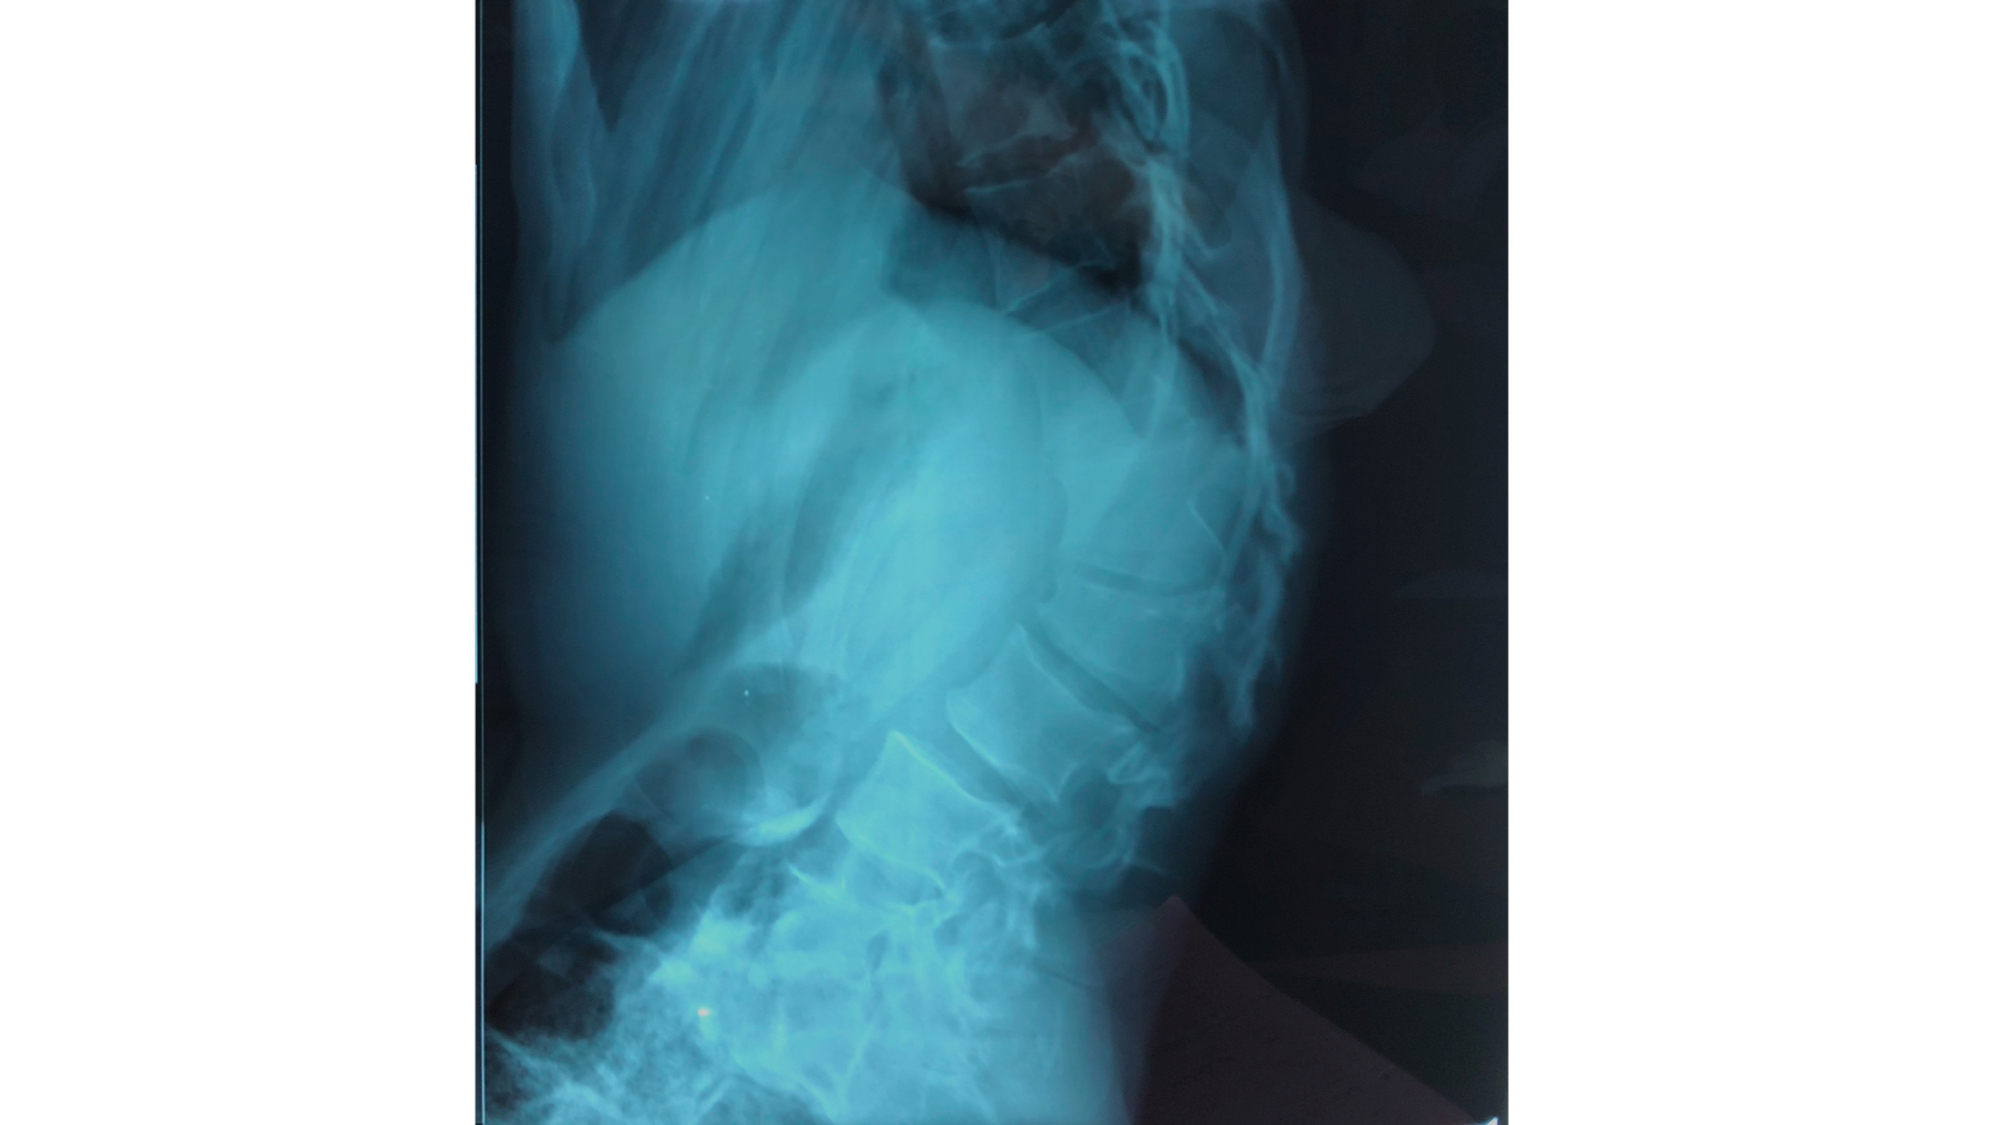

I was also able to meet the first two spine surgery fellows at AaBET. They are both neurosurgeons. The plan after next year is to alternate orthopedic with neurosurgery spine fellows. In addition to their teaching at AaBET, they are mentored by Dr Fasil Mesfin of Univeristy of Missouri, with whom they have weekly cases conferences. They were excited to show me two massive spine tumors they just operated on, one a giant, dumbbell shaped neurofibroma of the lower thoracic spine with bone involvement and preoperative paraparesis; the other a huge aneurysmal bone cyst of posterior lumbar element. Both needed pedicle screw instrumentation and big exposures. I am not a spine surgeon but the operative photos and postop xrays were very impressive.